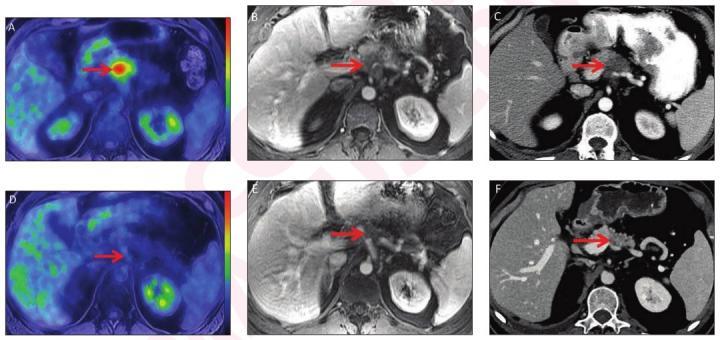

Combined pet/ct uses two imaging methods, ct and positron emission tomography (pet), in one procedure. Pancreatic cancer arises when cells in the pancreas, a glandular organ behind the stomach, begin to multiply out of control and form a mass. May be used to create and send images of your pancreas to a video monitor. Once in the hands of an oncologist who strongly suspects pancreatic cancer (based on. A ct scan can locate small tumors in the pancreas that might be.

In general, the more the cancer has grown and spread (the more advanced the cancer), the less chance that pancreatic cancer ct. Ct is done first to create anatomic pictures of the organs and structures in the body, and then pet is done to create pictures that provide functional data about the.